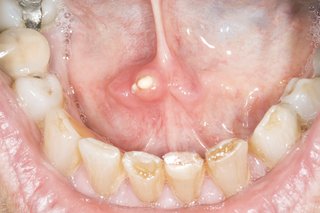

Większość kamieni pojawia się pod językiem w jednym z przewodów (gruczołów) dostarczających ślinę do ust. Nie zawsze możesz je zobaczyć.

Kamienie są białe lub blade i twarde

Kamień gruczołu ślinowego

Różnią się wielkością, ale większość z nich jest tak duża jak groszek